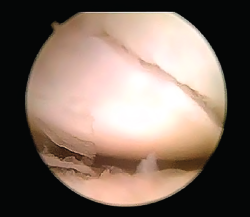

Se comienza la artroscopia en la articulación radiocarpiana a través del portal 3/4 con la colocación de la óptica para realizar un recorrido articular con el fin de identificar la existencia de lesiones asociadas o valorar fracturas del polo proximal del escafoides (Figura 8).

Figura 8. Visualización de la fractura de escafoides desde el portal 6R.